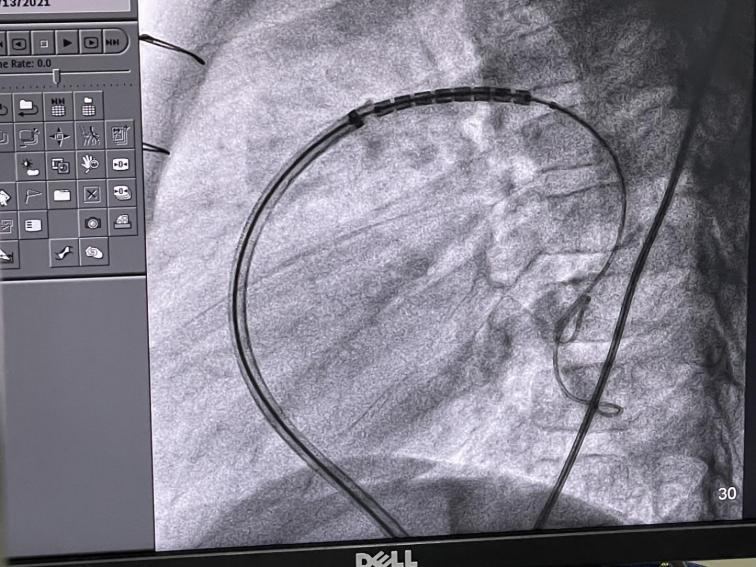

沿长鞘将支架送至狭窄处